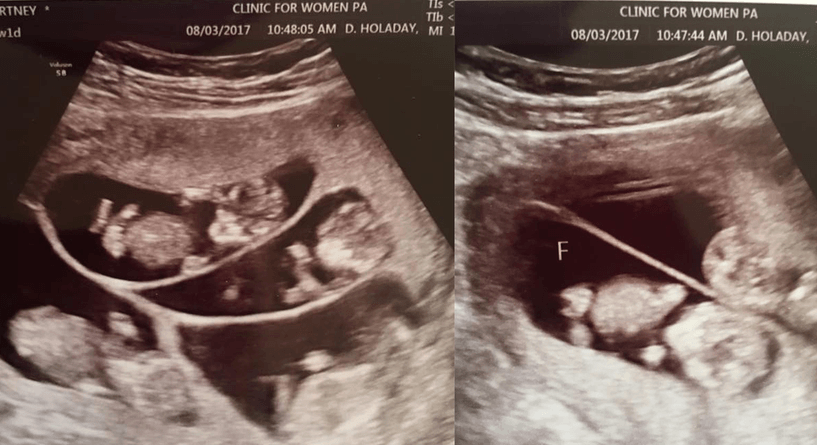

كورتني ولدروب امرأة أميركية أحبت وزوجها إريك انجاب طفل رابع يكمّل عائلتها المؤلفة من 3 اطفال الا أنها خسرت جنينها في بداية الحمل لتحل الصدمة على الثنائي بعد وقت وجيز وتعلم كورتني أنها حامل مجددًا وليس هذا فحسب بل انها حامل بـ توأم سداسي!

لم يكن الخبر مفاجئًا بقدر ما كان مقلقًا بالنسبة الى الثنائي فبصرف النظر عن التعب الذي سيسببه انجاب 6 اطفال في آنٍ واحد ناهيك عن تكاليف تربيتهم مع أطفال آخرين، فإن الحمل بهذا العدد من التوائم قد يشكل خطرًا عليهم وعلى والدتهم في الوقت عينه كما وأن حظوظ ولادتهم قبل أوانهم بفترة طويلة كبيرة أيضًا.

" الأمر مخيف نعم الا أنها نعمة كبيرة أن نكون والدين لـ9 اطفال يملأون حياتنا ضجيجًا، فرحًا وحبًا." بهذه الكلمات عبّر الثنائي عن مشاعرهما لدى تلقّيهما الخبر السعيد والصاعق في الوقت عينه. كورتني اليوم في الأسبوع الـ16 من حملها والأطباء يراقبون حالتها يومًا بعد يوم خوفًا من أي مشكلة قد تحدث وبخاصة أن كورتني قد سبق وتعرضت للإجهاض منذ فترة وجيزة.